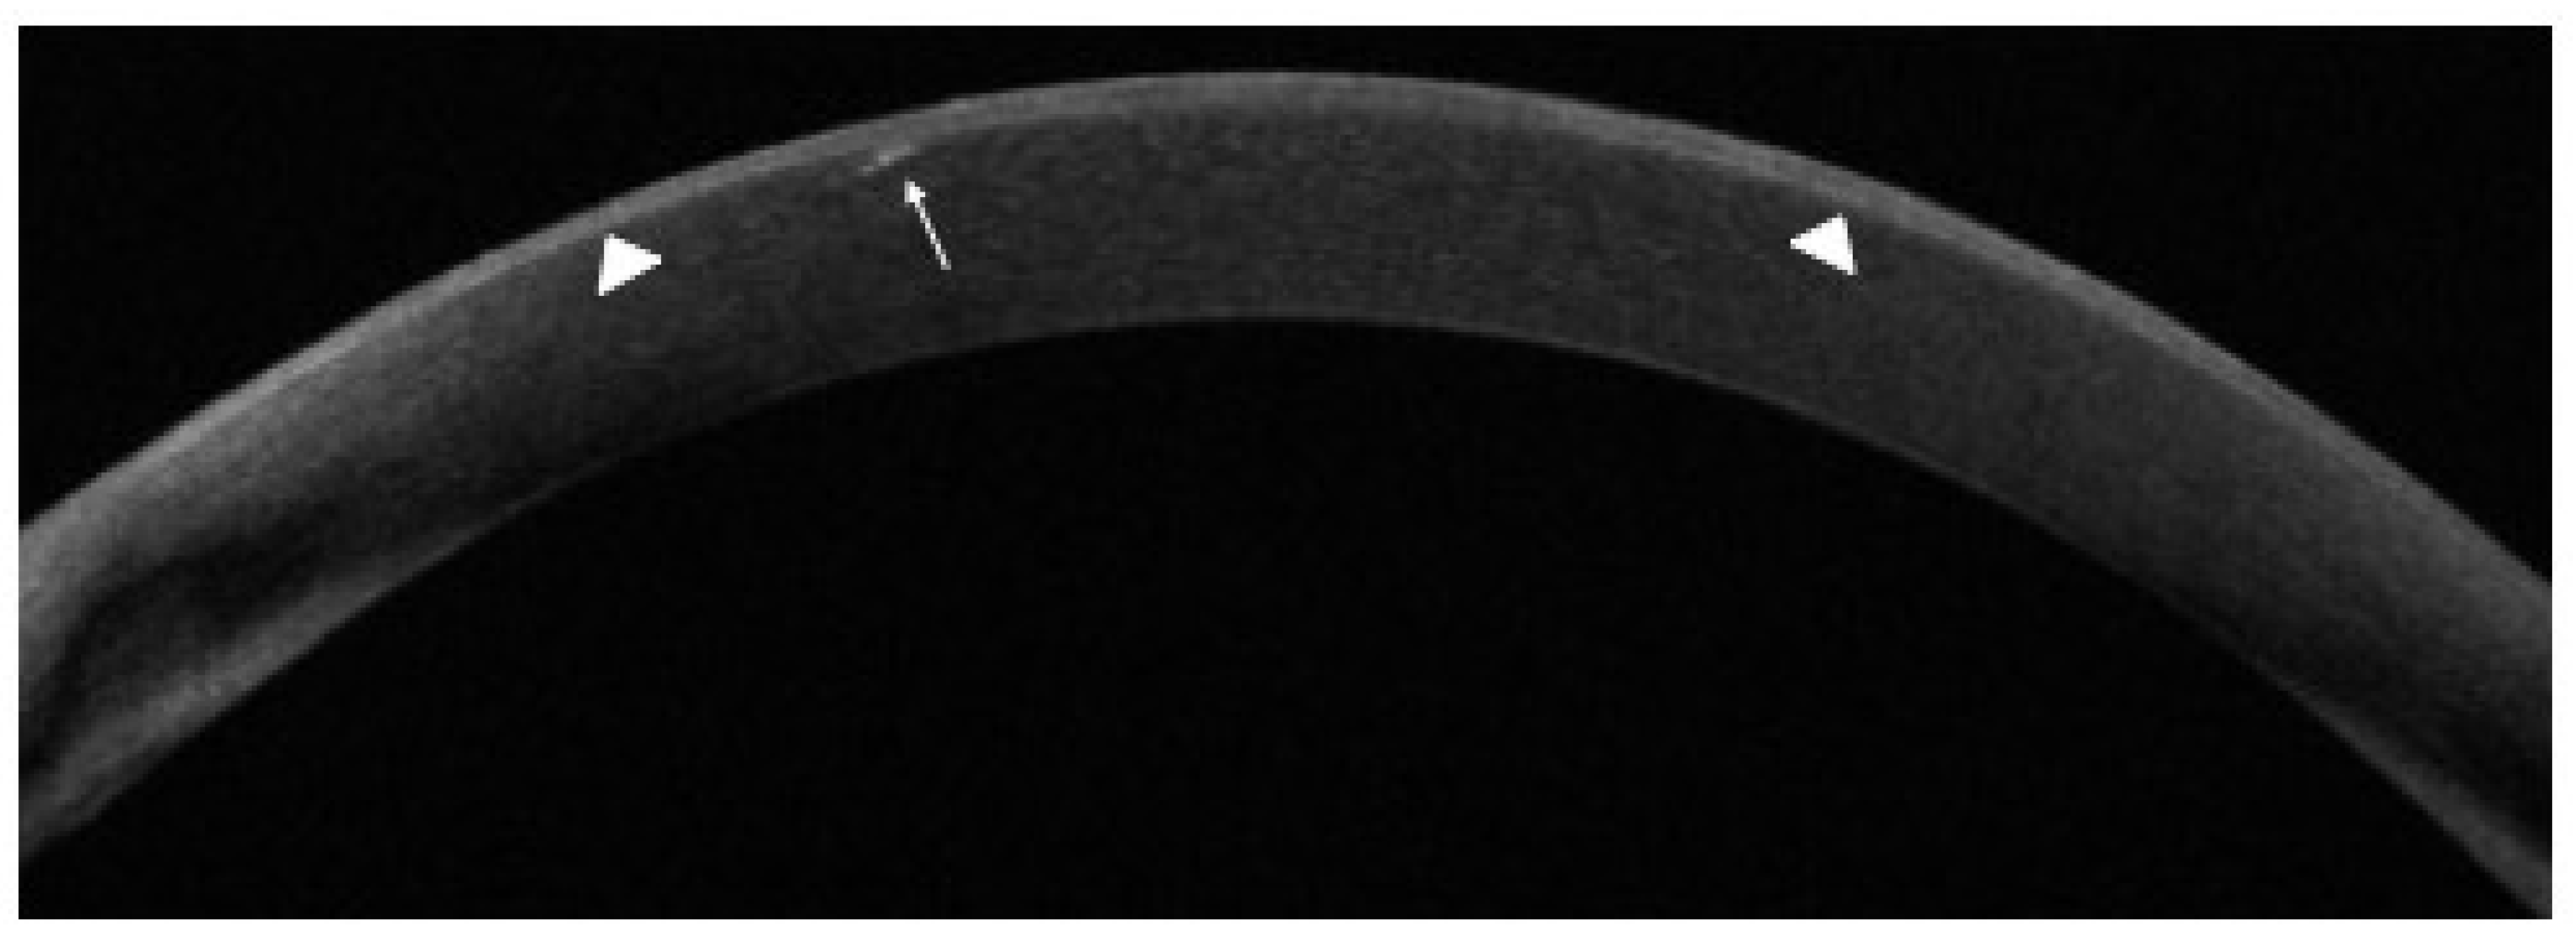

- Matsumiya, W.; Karaca, I.; Ghoraba, H.; Akhavanrezayat, A.; Mobasserian, A.; Hassan, M.; Regenold, J.; Yasar, C.; Liedtke, M.; Kitazawa, K.; et al. Structural changes of corneal epithelium in belantamab-associated superficial keratopathy using anterior segment optical coherence tomography. Am. J. Ophthalmol. Case Rep. 2021, 23, 101133. [Google Scholar] [CrossRef] [PubMed]